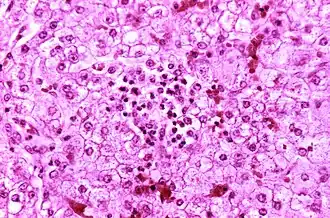

Синдро́м Ре́я, синдром Ре́йе (острая печёночная недостаточность и энцефалопатия, «белая печёночная болезнь») — редкое, но очень опасное, часто угрожающее жизни острое состояние, возникающее у детей и подростков (чаще в возрасте 4—12 лет) на фоне лечения лихорадки вирусного происхождения (грипп, корь, ветряная оспа) препаратами, содержащими ацетилсалициловую кислоту, и характеризующееся быстро прогрессирующей энцефалопатией (вследствие отёка головного мозга) и развитием жировой инфильтрации печени. Синдром Рея сопровождается гипераммониемией, повышением уровня АСТ, АЛТ в сыворотке крови (более чем в 3 раза) при нормальном уровне билирубина.

В основе синдрома лежит генерализованное повреждение митохондрий вследствие ингибирования окислительного фосфорилирования и нарушения β-окисления жирных кислот.